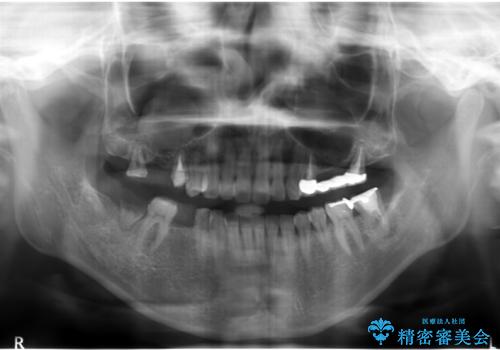

奥歯で咬むことができるようになり、また見た目も自然だと大変喜んで頂けました。

上顎骨がかなり薄くインプラント治療に対し望ましい状態でないことからも、自家歯牙移植は有意義であったと考えます。

右上奥歯の治療に関しても自家歯牙移植を希望され、現在治療中です。

被せ物の種類:メタルボンドクラウン エコノミー フルベイク